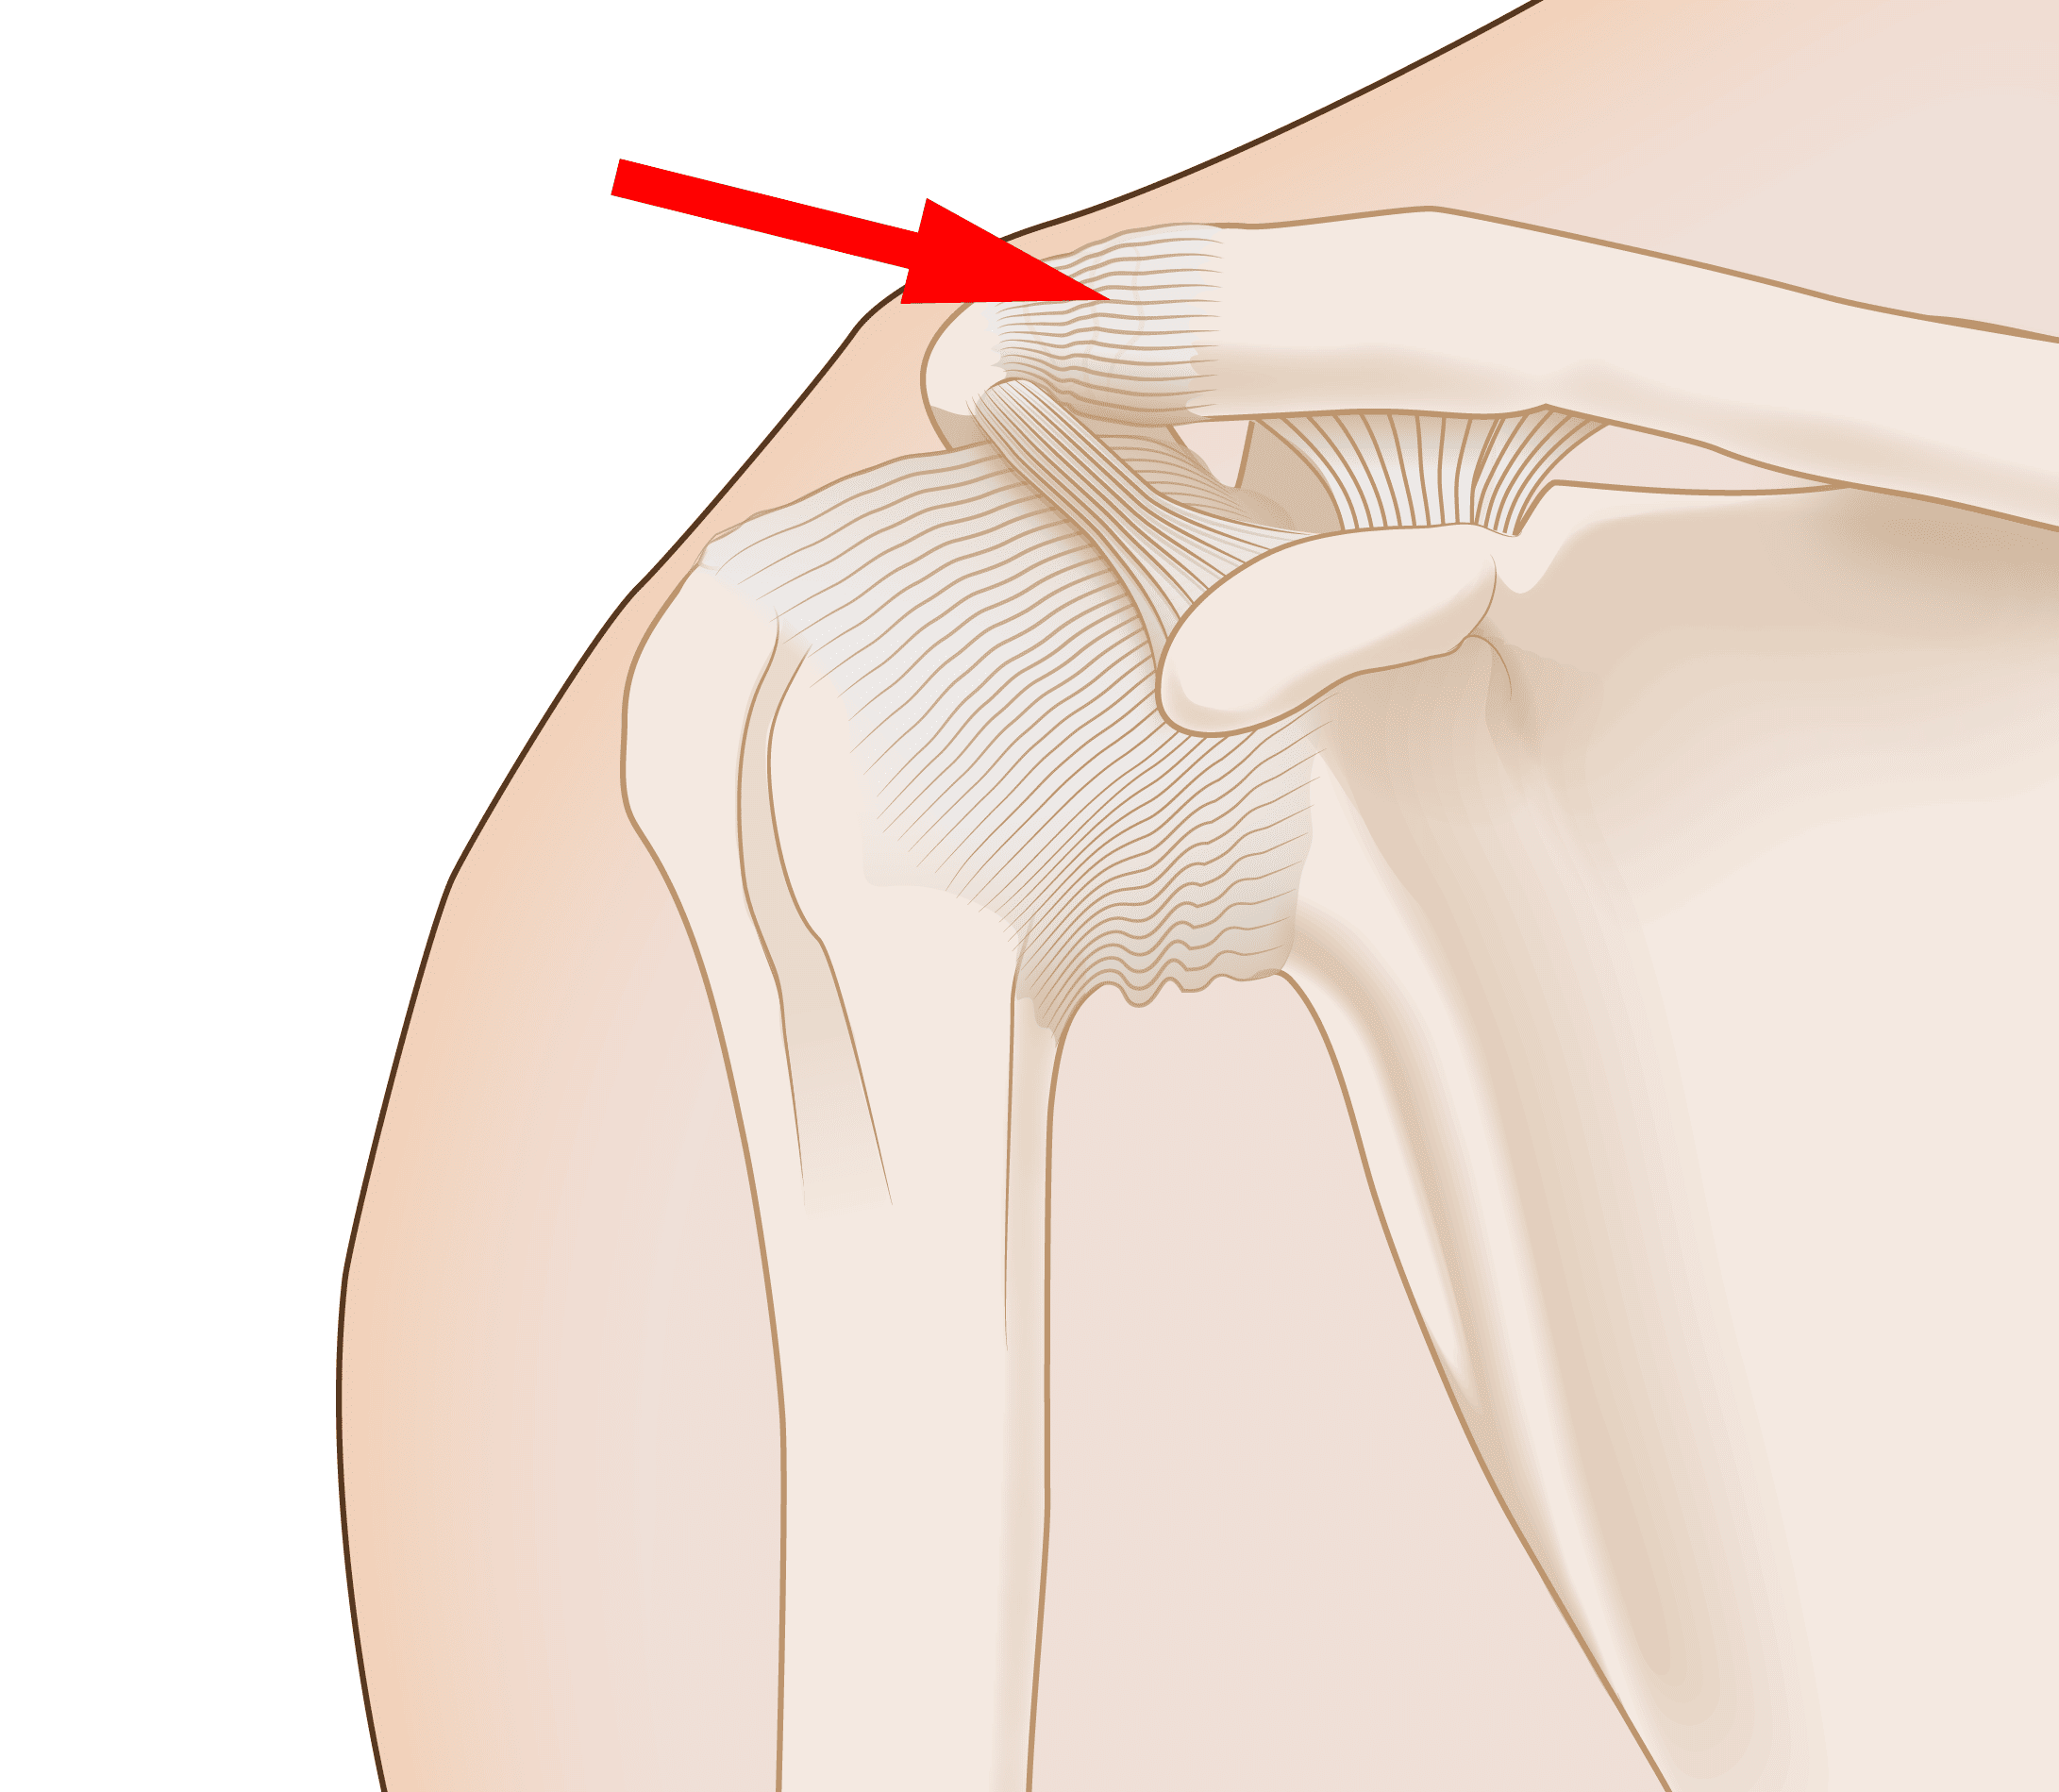

What Is Shoulder Separation Surgery . The injury actually involves the acromioclavicular joint (also called the ac joint). A shoulder separation is an injury to the area where ligaments hold your collarbone to the highest point of your shoulder blade, called the. Shoulder separations are acromioclavicular (ac) joint separations. A shoulder separation is not truly an injury to the shoulder joint. A separated shoulder is also medically known as an acromioclavicular (ac) joint separation. A separated shoulder, also known as acromioclavicular (ac) joint separation, occurs when the ligaments connecting your collarbone. It is commonly caused by a fall directly on the point of the shoulder or a direct. A shoulder separation injury happens when trauma damages the ligaments around the. It is a common injury that involves damage to the.

A shoulder separation is not truly an injury to the shoulder joint. It is commonly caused by a fall directly on the point of the shoulder or a direct. It is a common injury that involves damage to the. A separated shoulder, also known as acromioclavicular (ac) joint separation, occurs when the ligaments connecting your collarbone. Shoulder separations are acromioclavicular (ac) joint separations. The injury actually involves the acromioclavicular joint (also called the ac joint). A separated shoulder is also medically known as an acromioclavicular (ac) joint separation. A shoulder separation injury happens when trauma damages the ligaments around the. A shoulder separation is an injury to the area where ligaments hold your collarbone to the highest point of your shoulder blade, called the.

What Is Shoulder Separation Surgery A separated shoulder, also known as acromioclavicular (ac) joint separation, occurs when the ligaments connecting your collarbone. A shoulder separation is an injury to the area where ligaments hold your collarbone to the highest point of your shoulder blade, called the. A separated shoulder, also known as acromioclavicular (ac) joint separation, occurs when the ligaments connecting your collarbone. A shoulder separation is not truly an injury to the shoulder joint. It is commonly caused by a fall directly on the point of the shoulder or a direct. Shoulder separations are acromioclavicular (ac) joint separations. The injury actually involves the acromioclavicular joint (also called the ac joint). A separated shoulder is also medically known as an acromioclavicular (ac) joint separation. It is a common injury that involves damage to the. A shoulder separation injury happens when trauma damages the ligaments around the.